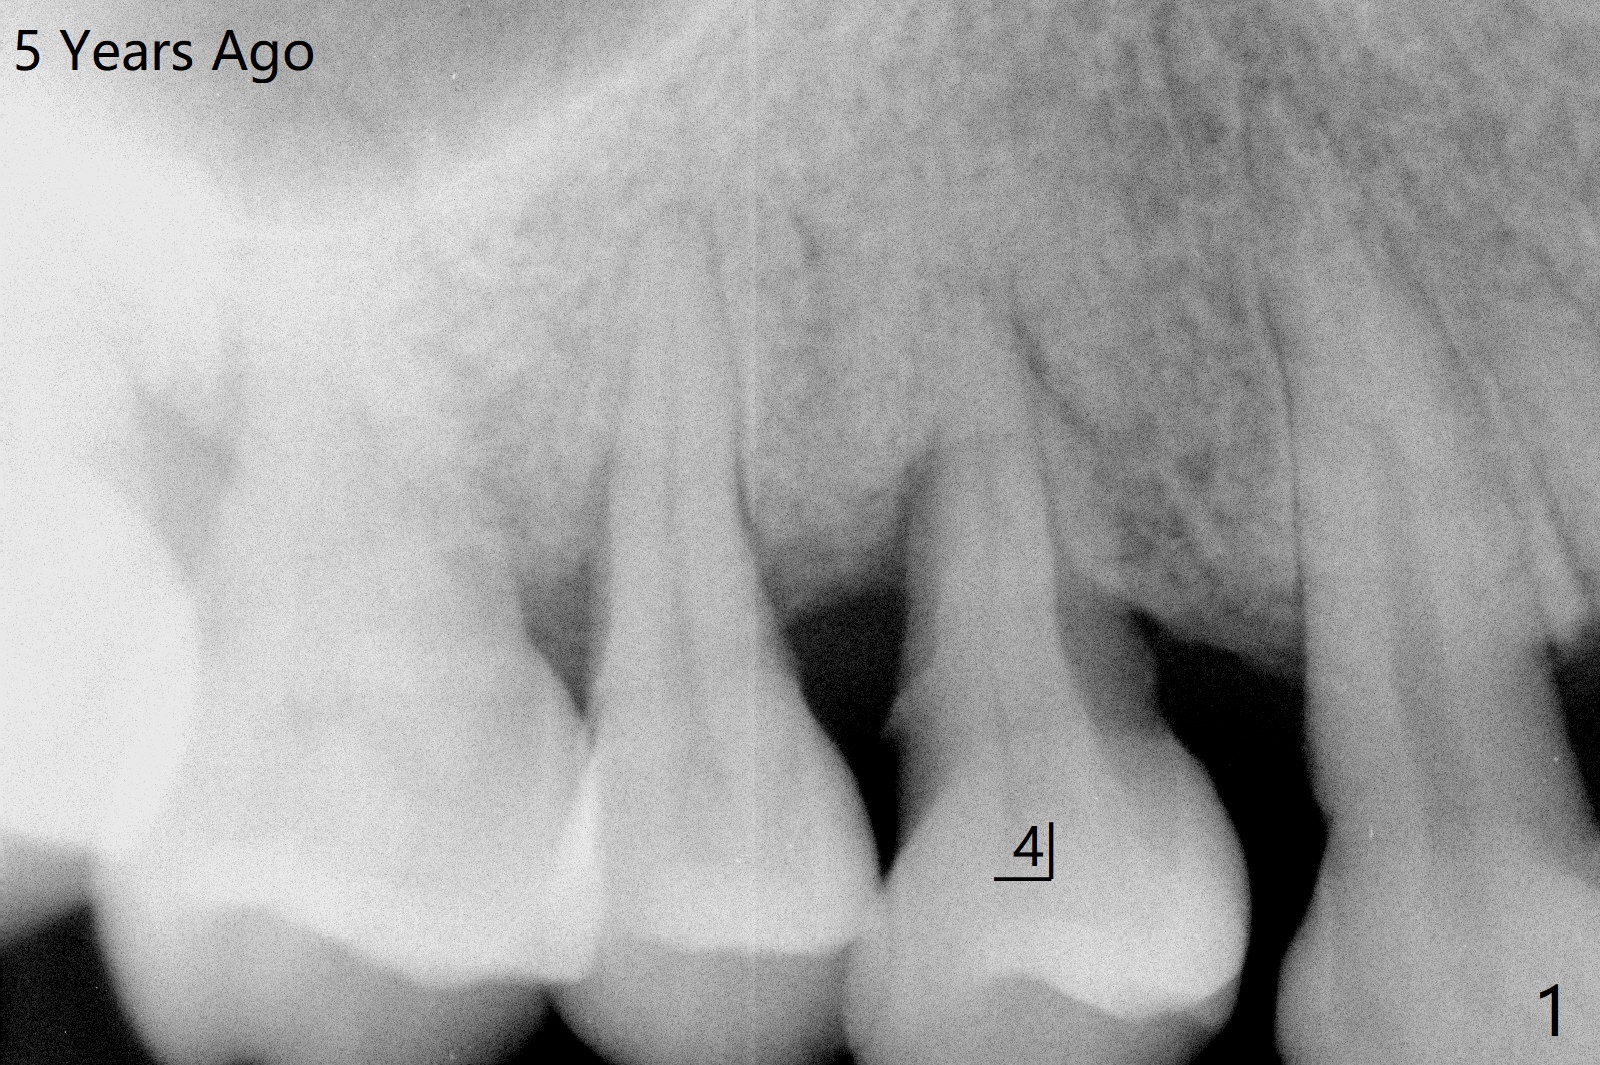

图三红线代表龈乳头,当两个邻牙拔除后,没有特殊处理,龈乳头不可避免收缩(图四)。如何预防呢?拔除4时,发现牙槽窝肉芽组织延申到牙槽嵴与乳头之间(图五:黄色)。刮治肉芽组织后,在空缺处,填入粘性骨粉(图六:圆圈),应该能够减少术后龈乳头萎缩。